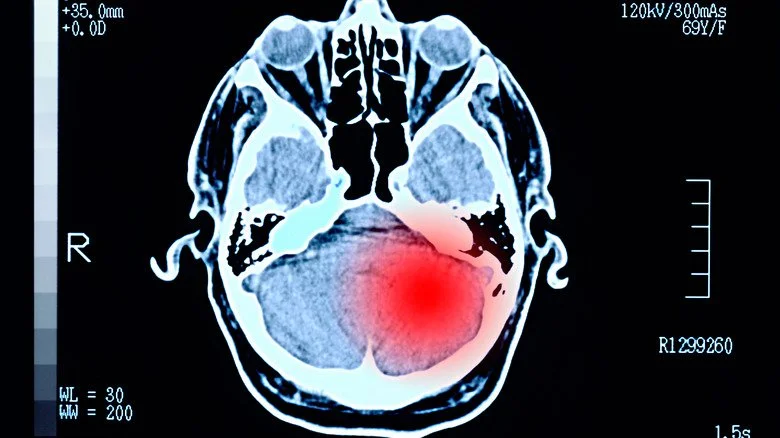

L’encéphalopathie traumatique chronique (ETC) a fait l’actualité ces dernières années en raison de sa prévalence apparente chez les joueurs de football, mais elle peut toucher quiconque a subi des traumatismes crâniens répétés. Bien que le mécanisme à l’origine de cette condition ne soit pas entièrement compris, des coups répétés à la tête, qualifiés de manière peu rassurante de « légères blessures cérébrales traumatiques », entraînent la mort des cellules cérébrales. Les symptômes se chevauchent avec ceux de plusieurs autres troubles, mais incluent des perturbations de l’humeur, des changements de personnalité, des difficultés à marcher et à maintenir l’équilibre, une perte d’autres compétences motrices et, le plus préoccupant, des pertes de mémoire et des troubles cognitifs.

Les ondes de choc provenant des explosions sont la source la plus fréquente de blessures cérébrales légères susceptibles de provoquer une ETC chez les militaires (et toute personne suffisamment malchanceuse pour se trouver dans une zone de guerre). Un rapport de l’Institut national de la santé (NIH) sur le trouble cite également les accidents de véhicule, les chutes, les incidents de formation et les loisirs comme des moyens par lesquels ces coups peuvent se produire. En plus de ses propres effets potentiellement dévastateurs, l’ETC semble augmenter le risque de maladies du motoneurone (comme la SLA, également connue sous le nom de maladie de Lou Gehrig) et de la maladie de Parkinson, qui peuvent, comme l’ETC, s’avérer mortelles. Malheureusement pour la recherche, l’ETC ne peut être diagnostiquée de manière définitive qu’au cours de l’autopsie.